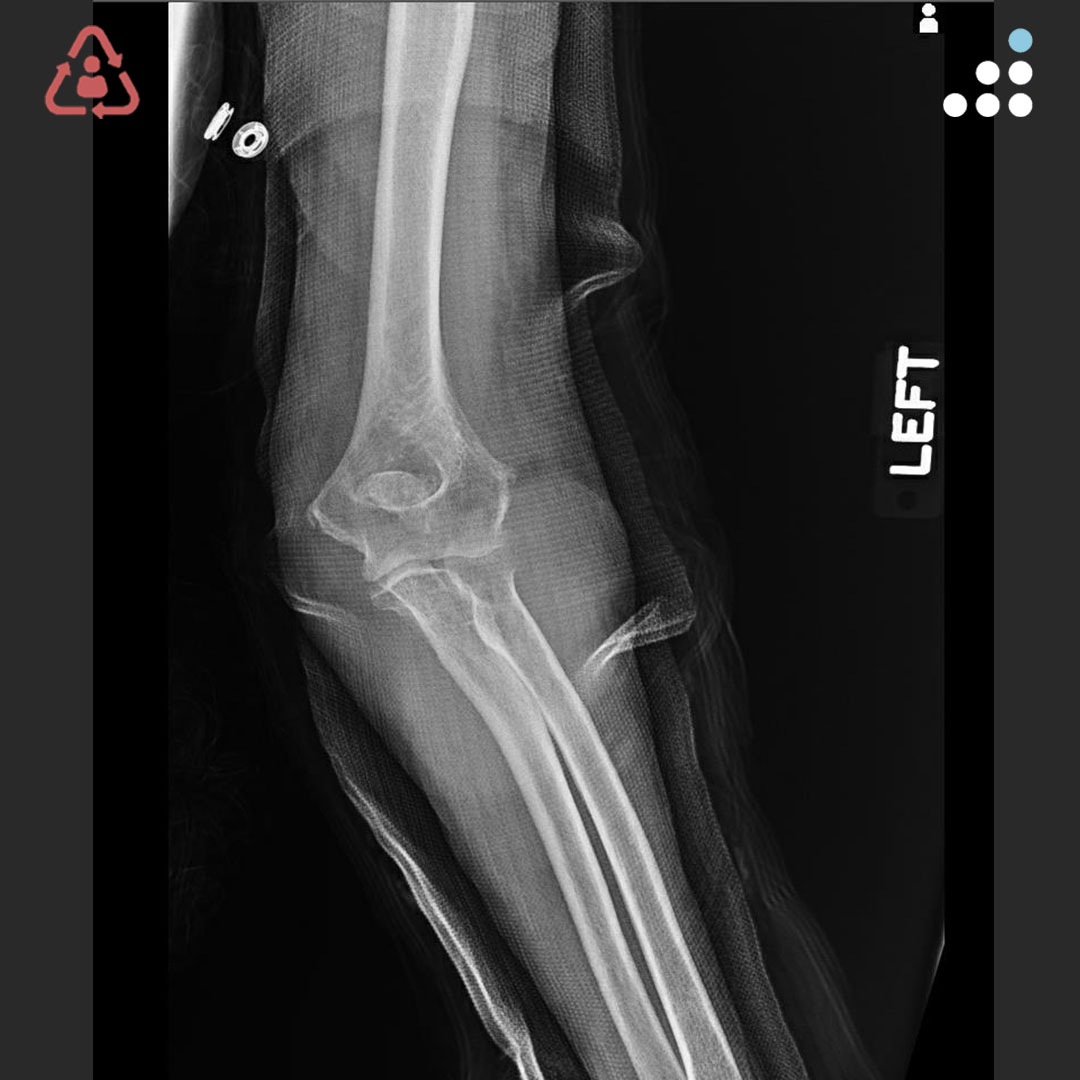

@orthobullets @KPSCALnews @rkh_md @DrMarecek @DeformityDoc @jamesablairMD @FractureDoc @stevemchale @traumaticum @DrFraneNicholas I am concerned about the +Fleck/flake sign. Get MRI or ultrasound to rule out a triceps rupture. If torn, I would perform ORIF and Triceps repair, after restoring the underlying metabolic issues. If the triceps is not torn, then would treat non-operatively.